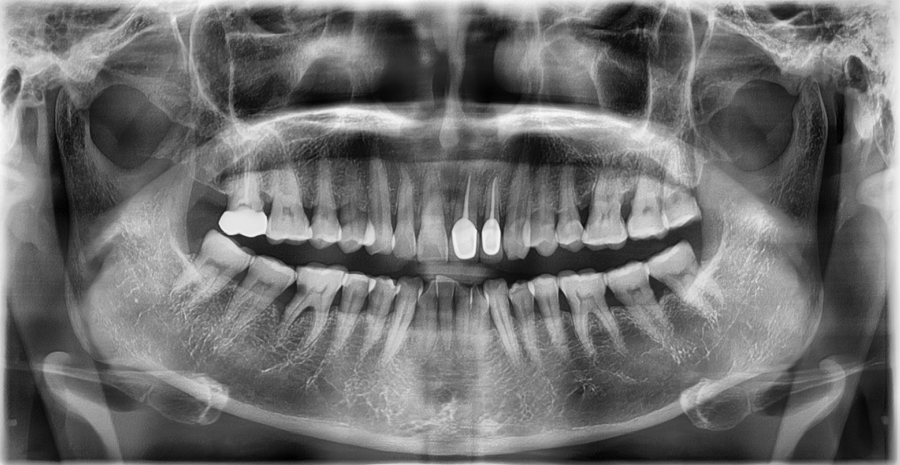

환자분은 앞니 보철 치료와 함께

어금니 임플란트 치료를 이미 받은 상태였습니다.

하지만 일상생활 중

• 임시 보철 사용 시 불안정한 느낌

• 찬물 섭취 시 시림

• 씹을 때 특정 부위에 힘이 몰리는 느낌

이 반복되면서

“이 상태로 계속 써도 되는 건지”에 대한

걱정이 점점 커진 상태로 내원하셨습니다.